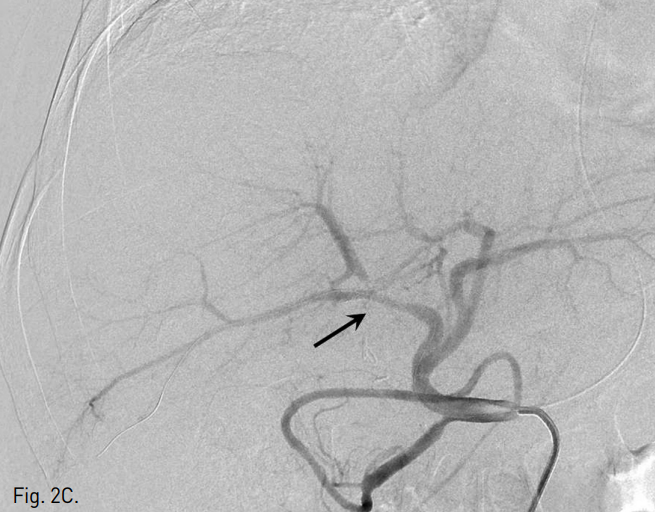

복강동맥조영술에서 우간동맥의 분지부에 인접한 위치에 가성동맥류를 확인하였다(Fig. 2A, B). 6F Shuttle guiding catheter(Cook, Bloomington, IN, USA)로 교체 후에 Stent-graft(4×26mm, JoStent GraftMaster®, JoMed, Germany)를 가성동맥류가 있는 우간동맥에 위치시키고, 풍선카테터(Ultra-thin Diamond,Boston Scientific, Galway, Ireland)를 사용하여 확장시켰다. 시술 직후 시행한 복강동맥조영술에서 동맥류는 관찰되지 않았다(Fig. 2C).

Fig. 2

Celiac (A) and hepatic angiogram (B) show the pseudoaneurysm (arrows in A and B) at distal part of the right hepatic artery near the origin of the right posterior hepatic artery. (C) On hepatic angiogram after stent-graft placement (arrow), the pseudoaneurysm is completely excluded.